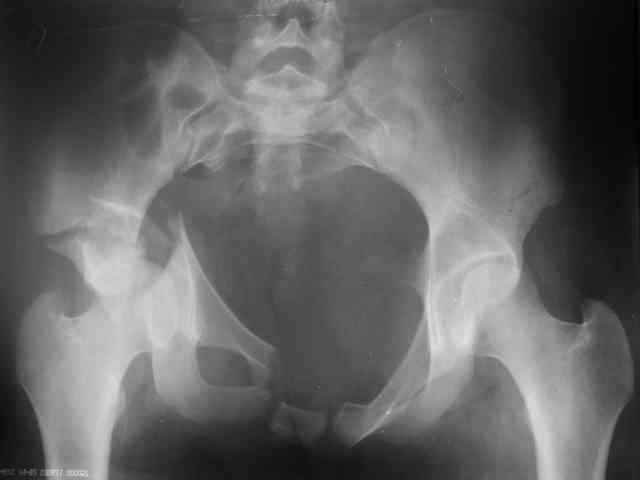

Re: acetabular fracture

Evgueny Tchekashkine 18 Сентябрь 2006, 23:01

Уважаемый Д-р Рунков( к сожалению, не знаю имени отчества),

Спасибо за отклик. Я вчера прооперировал больную.

Трудности возникли сразу после рассечения большой ягодичной мыцы - короткие наружные ротаторы едва ли определялись - головка и шейка (как видно на

снимке) ушли в таз, пришлось воспользоваться дистрактором( ручные попытки выдернуть голову из под проксимального фрагмента - безуспешны) Шарнирный дистрактор - великое изобретение, без него репозиция была просто невозможна.